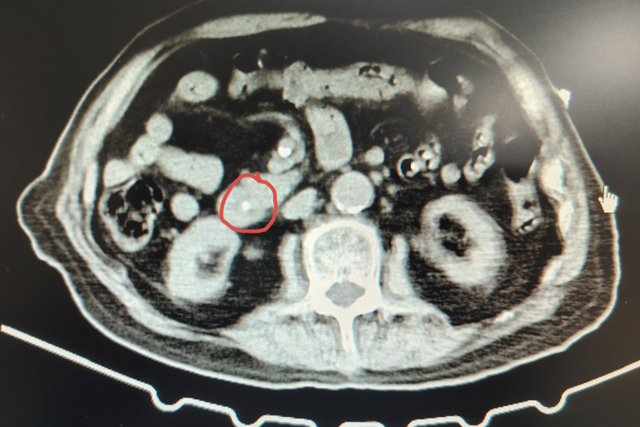

入院后抽血检查,发现张大爷肝功能指标全部异常,其中胆红素升高明显(总胆红素高达(TBIL)124.5μmol/L,直接胆红素(DBIL)74.8μmol/L,丙氨酸氨基转移酶(ALT)148U/L,碱性磷酸酶(ALP)和谷氨酰转氨酶(GGT)偏高),初步考虑可能是由于胆总管梗阻导致,进一步完善腹部CT检查,果然发现张大爷胆总管下端结石堵塞。

胆总管结石